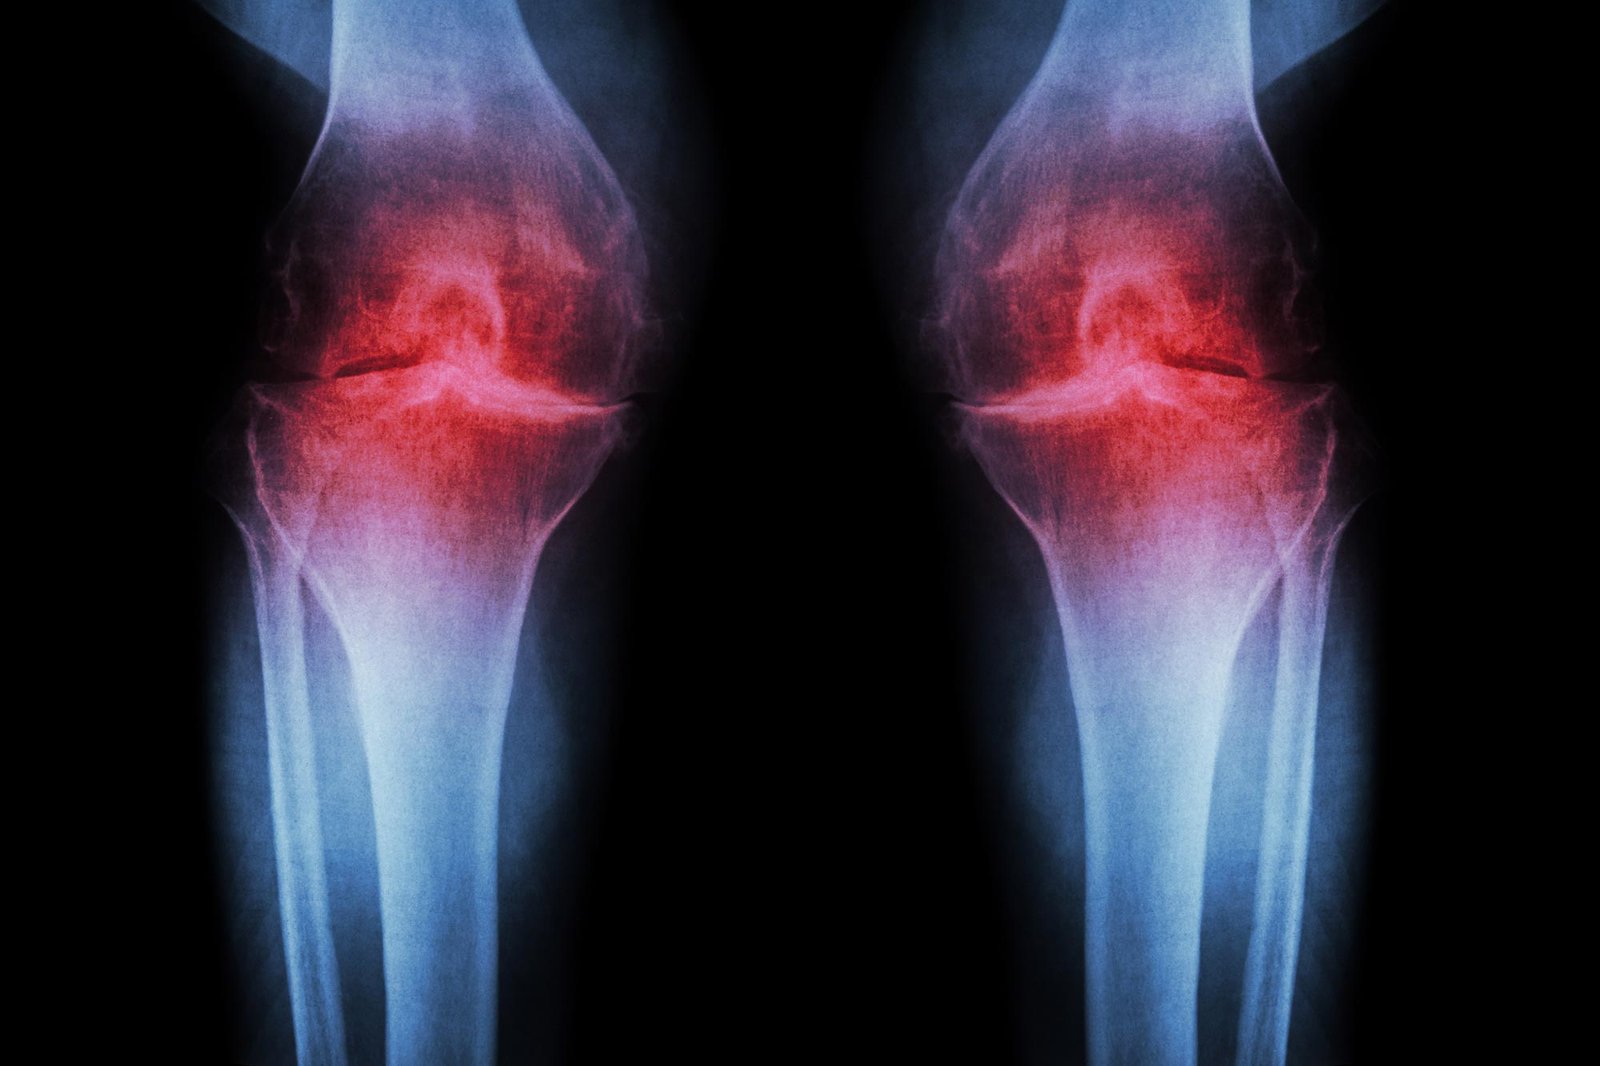

الحقن المضادة للشيخوخة تعيد نمو غضروف الركبة وتمنع التهاب المفاصل

العلاج الذي يمنع البروتين المرتبط بالعمر يعيد الغضروف في المفاصل المتقدمة في السن والمصابة عن طريق إعادة برمجة الخلايا الموجودة بدلاً من استخدام الخلايا الجذعية.

الباحثون في طب ستانفورد أفاد باحثون أن حجب البروتين المرتبط بالشيخوخة يمكن أن يعيد الغضروف الذي يتآكل بشكل طبيعي في ركبتي الفئران الأكبر سنًا. وفي الدراسة، لم يقتصر العلاج عن طريق الحقن على إعادة بناء الغضروف فحسب، بل أوقف أيضًا تطور التهاب المفاصل بعد إصابات الركبة المشابهة لتمزق الرباط الصليبي الأمامي، وهو أمر شائع بين الرياضيين والبالغين النشطين. ويجري بالفعل اختبار نسخة من العلاج نفسه تعتمد على حبوب منع الحمل في تجارب سريرية تهدف إلى علاج ضعف العضلات المرتبط بالشيخوخة.

هناك ثلاثة أنواع رئيسية من الغضروف في جسم الإنسان. الأول، الغضروف المرن، وهو ناعم ومرن ويشكل هياكل مثل الأذن الخارجية. أما النوع الثاني، وهو الغضروف الليفي، فهو كثيف وقوي، ويمتص الصدمات في مناطق مثل ما بين فقرات العمود الفقري. أما الثالث، وهو الغضروف الزجاجي، فهو أملس ولامع، ويوفر سطحًا منخفض الاحتكاك للتشحيم والمرونة في المفاصل مثل الكاحلين والوركين والكتفين وأجزاء من الركبة. الغضروف الهياليني — المعروف أيضًا باسم الغضروف المفصلي — هو الغضروف الأكثر تأثرًا بالتهاب المفاصل العظمي.

يحدث التهاب المفاصل العظمي عندما يتعرض المفصل للضغط بسبب الشيخوخة أو الإصابة أو السمنة. تبدأ الخلايا الغضروفية في إطلاق جزيئات مؤيدة للالتهابات وتكسير الكولاجين، وهو البروتين الهيكلي الأساسي للغضروف. عندما يتم فقدان الكولاجين، يرق الغضروف ويلين؛ ويسبب الالتهاب المصاحب تورم المفاصل والألم، وهي من السمات المميزة للمرض. في الظروف العادية، نادرا ما يتجدد الغضروف المفصلي. على الرغم من أنه تم التعرف على بعض مجموعات الخلايا الجذعية أو الخلايا السلفية القادرة على توليد الغضاريف في العظام، إلا أن محاولات تحديد مجموعات مماثلة من الخلايا في الغضروف المفصلي لم تنجح.